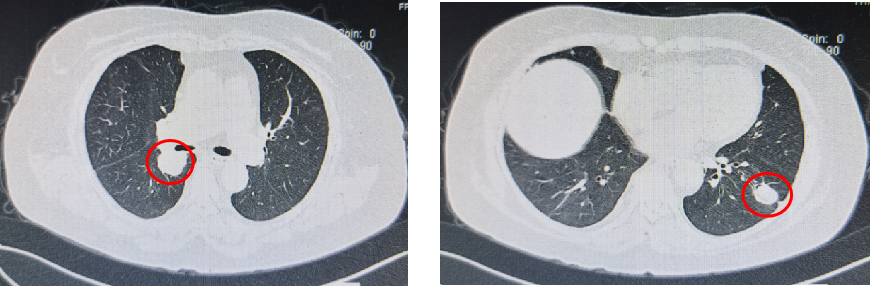

基本信息:性别 女,年龄 78岁,身高 159cm,体重 62kg。 主诉:结肠癌及肝转移瘤术后2年6个月(首次就诊时间为2018-09-10)。 既往史、个人史:“2型糖尿病”20年,予“二甲双胍 0.5g 口服 2次/日、门冬胰岛素注射液皮下注射,早 30U,晚 28U;甘精胰岛素皮下注射 20U ”降糖治疗,血糖控制一般。 家族史:无特殊。 02 初诊病史 体格检查、B超、CT及其他辅助检查。 体表面积1.60m,体格检查:浅表淋巴结未及肿大,双肺呼吸音粗,未闻及干湿性啰音,心律规整,未闻及杂音,腹壁可见陈旧性手术瘢痕,愈合良好,腹软,未及肿物,无压痛,肛查-,双下肢无水肿,起病隐匿,体检行腹部超声发现肝脏占位。 肠镜(2016-3-12):乙状结肠肿物。 咬检病理:(乙状结肠)腺癌。 肝胆胰增强CT(2016-3-10):肝左叶占位。 考虑:乙状结肠癌Ⅳ期 肝转移。 2016-3-21 于外院行“乙状结肠癌根治术+肝左叶转移瘤切除术”,术中予输血治疗,术后恢复慢,切口延期愈合。 术后病理:结肠中分化腺癌伴坏死形成,大者3.5cm×3.2cm×0.5cm,癌组织侵及浆膜脂肪层,脉管内癌栓形成,小者1cm×1cm×0.5cm,癌组织侵及粘膜下层。肠壁周围淋巴结癌转移(3/6),T3N1M1。(肝左叶)肝脏转移性腺癌伴大片坏死形成,大小6.6cm×6cm×4.5cm,结肠来源,残端及吻合口上下缘肠壁未见肿瘤侵及。 基因检测:KRAS、NRAS、BRAF 均未见突变。 初步诊断:乙状结肠癌Ⅳ期(pT3N1M1),同时性肝转移,中分化腺癌,2型糖尿病。 03 治疗方案 2016-4 XELOX 方案化疗1周期(具体剂量不详)因不良反应较重,未完成术后辅助治疗疗程。未予后续治疗,定期复查,病情稳定 胸腹CT(2017-3-19 ):右肺下叶新结节,考虑转移;肝左外叶转移瘤切除术后改变。 2017-4-1 于外院行局部肺肿物射频消融术,无治疗反应,恢复良好。 胸CT(2017-12-5):肺部新发结节,考虑转移。 【一线治疗方案(2017-12至2018-9)】 卡培他滨 1.5g po d1-14 q3w,共10个周期。 不良反应:1度消化道反应。 期间疗效评价:SD。 胸腹增强CT(2018-9-11):符合结肠癌切除术后,肝左叶切除后改变,双肺多发结节,部分较前增大。 2017-12-5 2018-9-11 建议调整方案治疗,患者家属拒绝,继续口服卡培他滨至2019年3月。 疗效评估: ECOG PS评分1分,新发活动后胸闷、气短症状 胸腹平扫CT(2019-3-26):双肺多发结节,较前增大;肝左外叶转移瘤切除术后改变。 2018-9-11 2019-3-26 评估PD。 【二线治疗方案(2019-4至2020-5)】 贝伐珠单抗 300mg ivgtt d0(体重62kg); 卡培他滨 1.5g po d1-14 q3w,共15周期。 不良反应:1级高血压、1度消化道反应。 疗效评估: 胸腹CT(2020-5-21):符合结肠癌术后、肝左叶切除术后,肝左切缘旁异常密度灶,左髂总动脉旁淋巴结;双肺多发结节,部分较前增大,右肺门肿物较前增大。 疗效评价:PD。 【三线治疗方案(2020-5至2020-10)】 西妥昔单抗 600mg ivgtt d0(体表面积1.66 m2); 亚叶酸钙 500mg ivgtt d1; 氟尿嘧啶 500mg ivgtt ,随后3500mg iv泵入 q2w,共9周期。 不良反应:无皮疹、腹泻、恶心、呕吐等。 疗效评估: 胸腹平扫CT(2020-09-07):右肺下叶背段软组织肿块,较前略减小,双肺多发小结节,转移瘤,同前;结肠癌术后、肝左叶切除术后改变,肝左切缘旁异常密度灶同前相仿,腹膜后左侧髂总动脉旁淋巴结同前。 2020-7-23 2020-9-7 疗效评价:SD(缩小趋势)。 胸腹平扫CT(2020-10-24):右肺下叶背段软组织肿块,较前(2020-9-7)略减小,双肺多发小结节,转移瘤,部分较前减小,结肠癌术后、肝左叶切除术后改变,肝左切缘旁异常密度灶同前相仿,腹膜后左侧髂总动脉旁淋巴结同前。 2020-9-7 2020-10-24 疗效评价:SD(缩小趋势)。 胸腹平扫CT(2020-12-13):右肺下叶背段软组织肿块,较前(2020-10-24)未见著变,双肺多发小结节,转移瘤,较前未见著变,结肠癌术后、肝左叶切除术后改变,肝左切缘旁异常密度灶同前相仿,腹膜后左侧髂总动脉旁淋巴结同前。 2020-12-13 疗效评价:SD。 患者未规律返院行西妥昔单抗维持治疗。 胸腹增强CT(2021-1-5):右肺下叶背段软组织肿块,较前(2020-12-13)增大,双肺多发小结节,转移瘤,左肺尖结节较前增大,余未见著变,左侧髂总动脉旁淋巴结较前增大。 疗效评价:PD。 【四线治疗方案(2021-1至2021-10)】 安罗替尼 8mg po 1次/日 d1-14 (2021-3 起因高血压2级,药物控制不佳调整为8mg qod ); 卡培他滨 1g po 2次/日 d1-14 q3w (2021-4 起因乏力2级不能耐受停服)。 不良反应:2级高血压,2级乏力,1级胆红素升高,1度消化道反应。 疗效评估: 胸腹增强CT(2021-10-3):右肺下叶背段占位,考虑恶性肿瘤,较前增大,双肺多发转移瘤,部分较前略增大,结肠癌术后、直肠区肠管明显扩张,肝左叶切除术后改变,切缘旁占位伴肝内胆管扩张,累及胆总管,考虑恶性病变,较前增大,腹膜后左侧髂总动脉旁淋巴结,较前增大,累及左侧输尿管伴以上输尿管及肾盂扩张。 2021-10-3 疗效评价:PD。 疗效评估: 胸腹增强CT(2021-10-3):右肺下叶背段占位,考虑恶性肿瘤,较前增大,双肺多发转移瘤,部分较前略增大,结肠癌术后、直肠区肠管明显扩张,肝左叶切除术后改变,切缘旁占位伴肝内胆管扩张,累及胆总管,考虑恶性病变,较前增大,腹膜后左侧髂总动脉旁淋巴结,较前增大,累及左侧输尿管伴以上输尿管及肾盂扩张。 【后线治疗方案(2021-10至2021-11)】 曲氟尿苷替匹嘧啶片(TAS-102) 40mg po 2次/日 d1-5,d8-12,q4w; 贝伐珠单抗 200mg ivgtt q2w。 不良反应:无皮疹、腹泻、恶心、呕吐等。 疗效评估: 胸腹增强CT(2021-11-17):右肺下叶背段占位,较前变化不明显,双肺多发转移瘤,较前变化不明显,结肠癌术后、直肠区肠管明显扩张,肝左叶切除术后改变,切缘旁占位伴肝内胆管扩张,累及胆总管,考虑恶性病变,较前变化不明显,腹膜后左侧髂总动脉旁淋巴结,较前减小,肾盂扩张较前减轻。 疗效评价:SD。 胸腹增强CT(2021-11-17):右肺下叶背段占位,较前变化不明显,双肺多发转移瘤,较前变化不明显,结肠癌术后、直肠区肠管明显扩张,肝左叶切除术后改变,切缘旁占位伴肝内胆管扩张,累及胆总管,考虑恶性病变,较前变化不明显,腹膜后左侧髂总动脉旁淋巴结,较前减小,肾盂扩张较前减轻。 04 病例小结 患者为高龄女性,诊断为直肠癌Ⅳ期多发转移,KRAS、NRAS、BRAF 均未见突变。 OS为69个月。